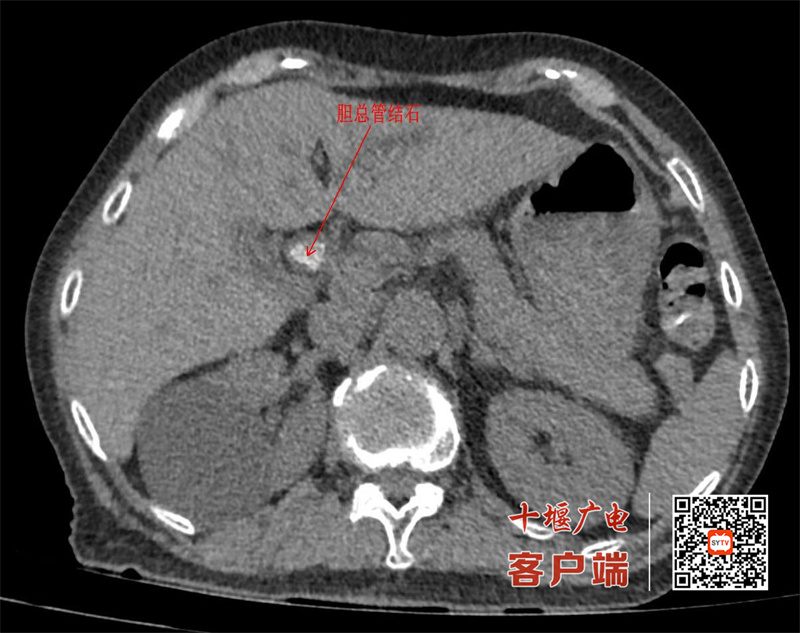

今年80岁的黄先生(化姓)有着多年的结石病史,去年已因胆囊结石切除胆囊。本月初,他再次突发剧烈腹痛,伴皮肤巩膜黄染,被紧急送至市中西医结合医院普外科。检查提示胆总管内多发结石并完全梗阻,肝功能指标明显异常,且患者高龄、既往两次腹部手术史,常规开腹风险极高。

“我们当即决定采用ERCP这一‘超级微创’路径。”市中西医结合医院普外科主任曹扶胜介绍,ERCP手术经口腔、食管、胃自然腔道置入十二指肠镜,在X线监视下将导管导丝精准插入胆总管,完成造影、碎石、网篮取石,全程无切口、出血量不足5毫升,用时仅30分钟。